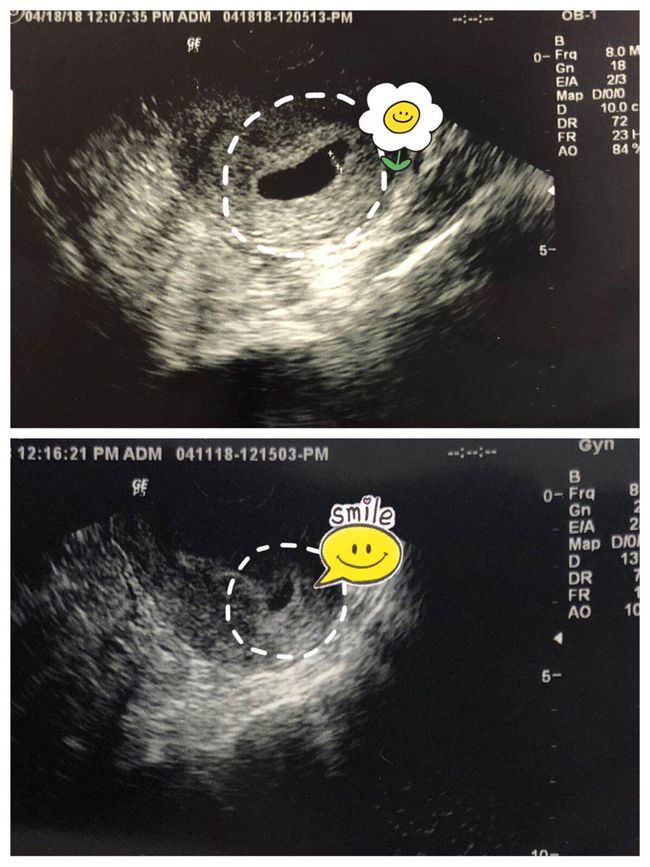

3. 影像学检查:B超、CT、MRI等影像学检查可以帮助医生观察子宫、卵巢、输卵管等器官的形态和血流情况,从而判断是否存在异位妊娠。